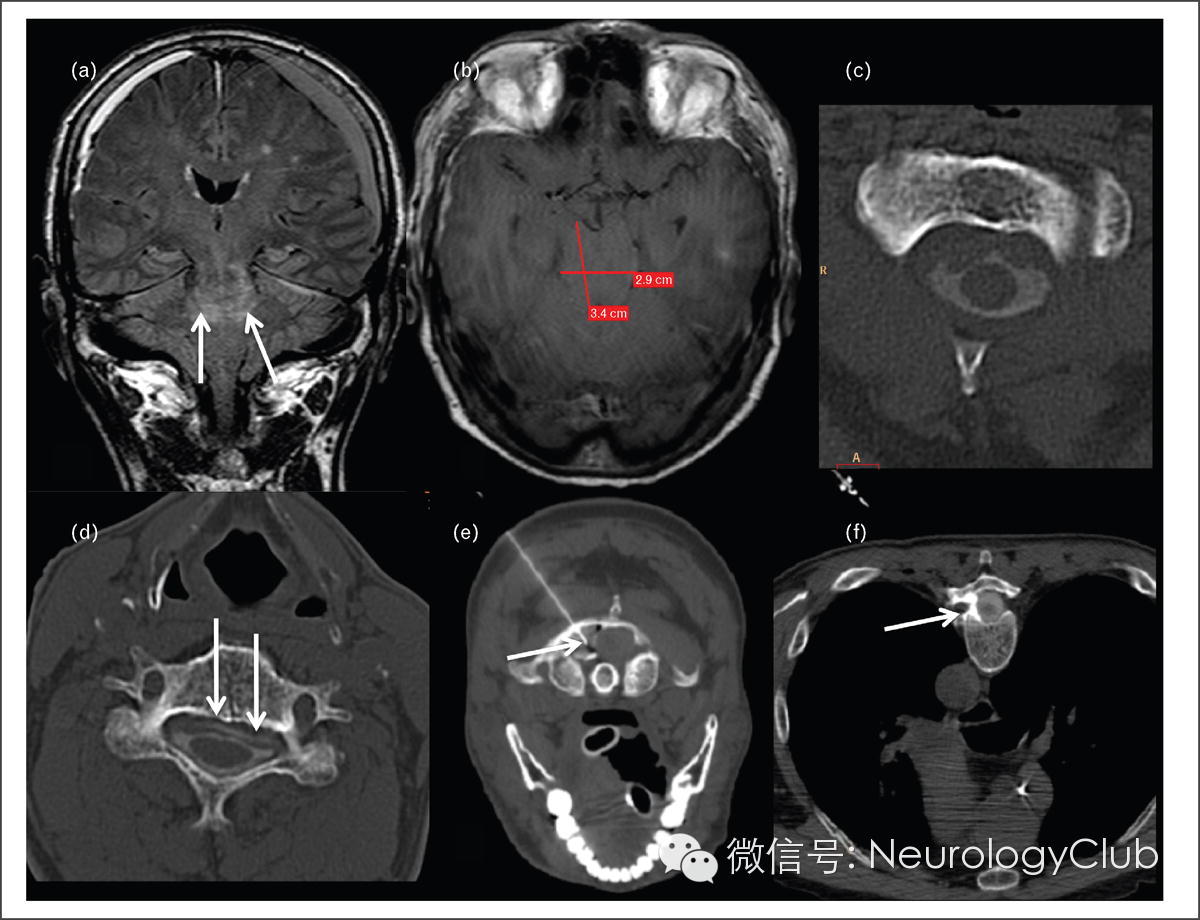

图2 术后低颅压相关的昏迷

71岁男性,硬膜下血肿清除术后发生昏迷。冠状位FLAIR(图a)显示广泛硬膜下渗出和脑干上部的信号改变(箭),横断位T1WI(图b)显示中脑的前后径变大,左右径变小。脊髓CT(图c,d)见囊内脑脊液稀少,颈胸段脊髓硬膜外存在造影剂渗漏(箭,图d)。该病人在CT引导下行纤维蛋白注射术,手术部位为C1/C2,T3/4,T6/7交界处水平。患者数天内意识恢复且只遗留轻微的左手协调能力缺损。